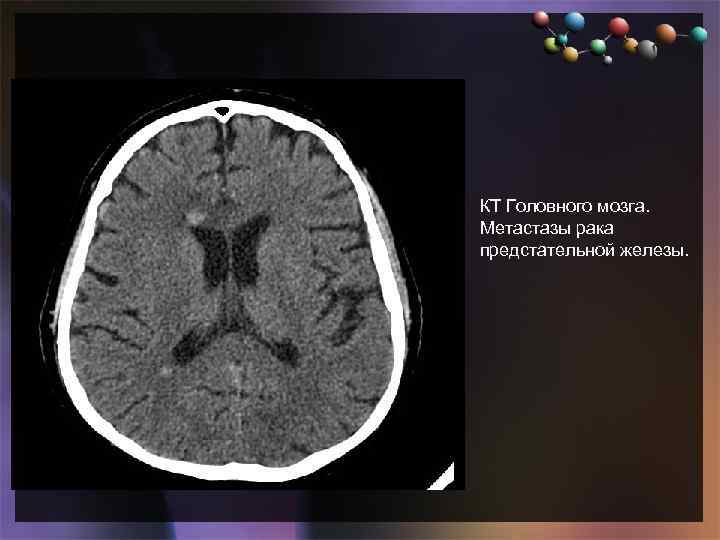

• Подзаголовок слайда КТ Головного мозга. Метастазы рака предстательной железы.

• Подзаголовок слайда КТ Головного мозга. Метастазы рака предстательной железы.